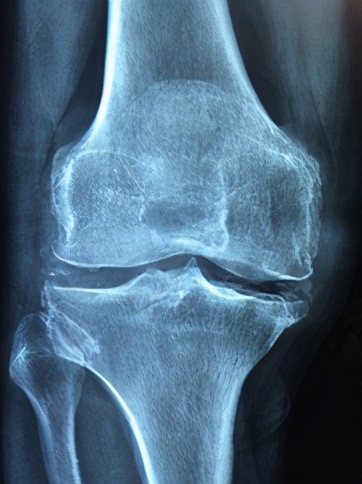

风湿性关节炎(rheumatic arthritis)是一种常见的急性或慢性结缔组织炎症。通常所说的风湿性关节炎是风湿热的主要表现之一,临床以关节和肌肉游走性酸楚、红肿、疼痛为特征。与A 组乙型溶血性链球菌感染有关,寒冷、潮湿等因素可诱发本病。

人体各部分都分布着经络,经络内联脏腑,外布体表肌肉,是联接内外,调节机体正常运行的关键。而从风湿关节炎的病因看,寒与湿都会一定程度上使经络受阻,而艾灸相应的穴位,就可起到疏通经络,调和气血,平衡功能的作用,起到增强人体抗病能力的作用。